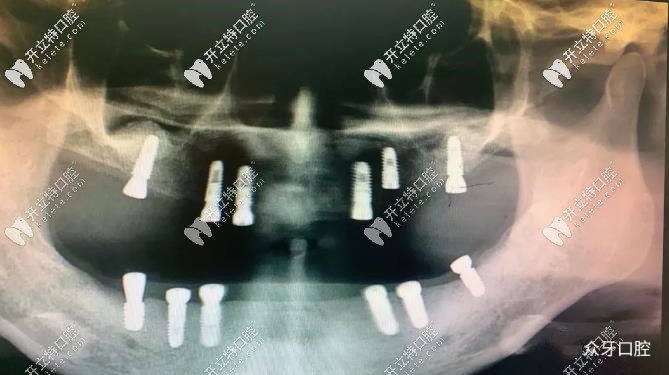

太原眾牙口腔——58歲阿姨,上下頜各種6顆種植體-CT片▲

經(jīng)過專業(yè)的檢查后,我院盧院長為李女士制定了種植方案,采用半口種植技術(shù):上下頜各植入6顆種植體;講解了手術(shù)方案后,李女士表示認可,手術(shù)順利開始。